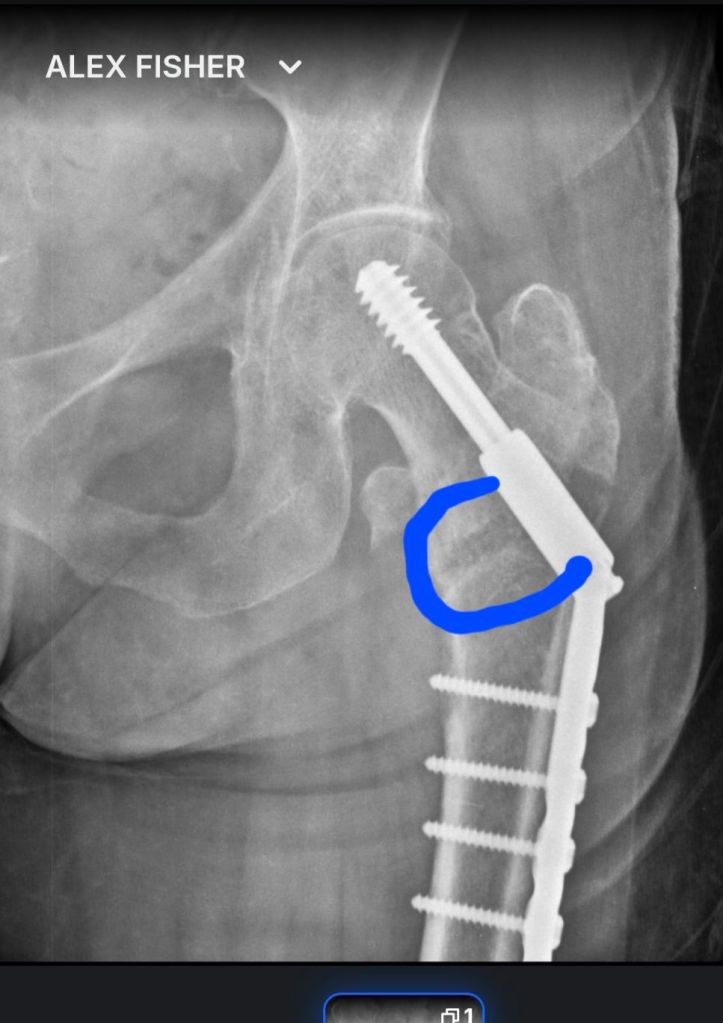

After ten months of recovering from an accident where I broke my femur and had surgery, I get down quite often. I want to be able to walk without pain or limping. The other day, in a tearful fit of feeling sorry for myself, Lisa reminded me how far I’ve come and said, “you’re doing great, you’re still healing .”